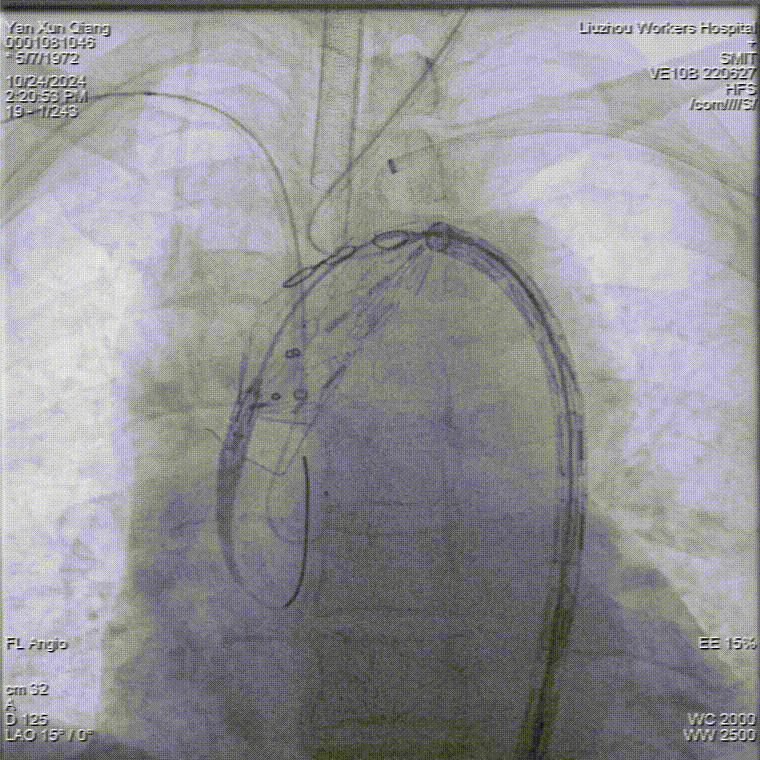

术后造影,支架形态良好,分支血流通畅